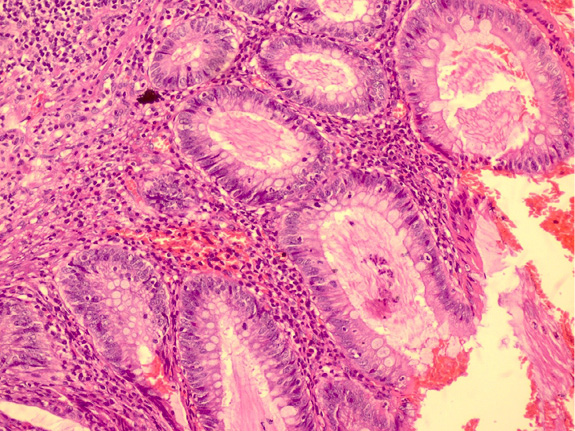

Pathologically, the appendix lumen diameter was 1.7 cm in the widest area. The appendix’s long axis was 7.5 cm. Mucoid material was observed in the lumen. The pathologic diagnosis was low-grade appendiceal mucinous neoplasm (appendiceal villous adenoma). Villiform mucinous epithelial proliferation was observed to replace the normal appendix mucosa [Figure 2]. It was observed that lymphoid tissue decreased In lamina propria and was replaced with fibrotic connective tissue [Figure 3]. Villiform mucinous epithelial proliferation appears to be composed of long mucinous epithelial cells with a low degree of nuclear atypia [Figure 4].

Figure 4. Villiform mucinous epithelial proliferation consisting of long mucinous epithelial cells with low degree of nuclear atypia